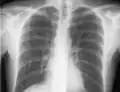

The line is then inserted using the Seldinger technique: a blunt guidewire is passed through the needle, then the needle is removed. A dilating device may be passed over the guidewire to expand the tract. Finally, the central line itself is then passed over the guidewire, which is then removed. All the lumens of the line are aspirated (to ensure that they are all positioned inside the vein) and flushed with either saline or heparin.[1] A chest X-ray may be performed afterwards to confirm that the line is positioned inside the superior vena cava and no pneumothorax was caused inadvertently. On anteroposterior X-rays, a catheter tip between 55 and 29 mm below the level of the carina is regarded as acceptable placement.[37] Electromagnetic tracking can be used to verify tip placement and provide guidance during insertion, obviating the need for the X-ray afterwards.

Chest x-ray with catheter in the right subclavian vein

The outline of superior vena cava on a chest X-ray is labeled at left.